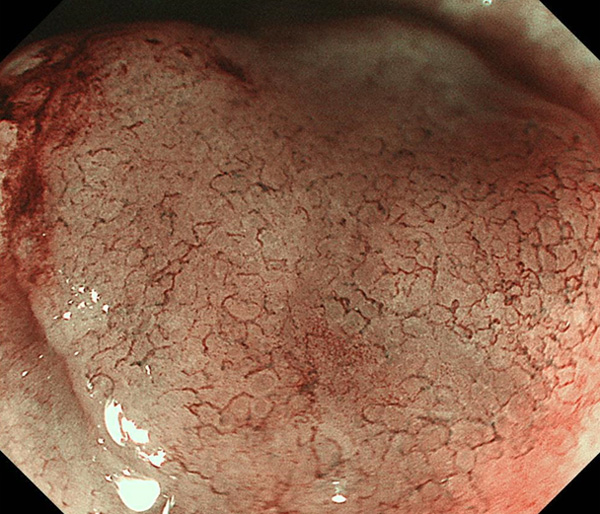

内視鏡所見と病理組織像の1対1対応が可能な症例を公募いたします。主にLSBEに発生した早期癌(HGDを含む)を対象としますが、興味深い症例であればSSBE癌でも結構です。採否は世話人へご一任ください。

特に、本邦では極めて稀なlong segment Barrett’s esophagus(LSBE)から発生した早期癌は、診断に難渋する場合も多く、欧米ではランダム生検による検出が標準的とされています。背景のBarrett食道もろとも全体を内視鏡切除+ラジオ波焼灼する欧米と異なり、ESDで内視鏡的な局所切除が基本の本邦では、存在診断+範囲診断(特に水平)を的確に行うことが不可欠です。

そのためには、一流の病理医による組織学的診断とエキスパート内視鏡医による拡大内視鏡像との一対一対応を徹底的に行うことで、『本来、見えないであろう拡大所見の先にある組織構築像が診えてくる』所まで内視鏡診断レベルを上げていく必要があります。その実現には、一対一対応を追究した症例(特にLSBE発生例)1例でも多く経験するしかありません。本研究会でBarrett食道腺癌(LSBE発生早期病変)を共に学び、拡大内視鏡像の一歩先を診るスキルを習得しましょう!一人でも多くの皆様のご参加をお待ちしています。

私は、Barrett食道癌はHGDも含め、内視鏡による存在診断、範囲診断が可能と信じて来ました。しかし最近、NBI拡大観察を併用しても側方範囲診断が不可能なLSBE症例を経験しました。診断技術を向上させるためには、多くの症例を診るしかありません。そこで、Barrett食道に造詣の深い先生方に世話人をお願いし、Barrett食道研究会を立ち上げることに致しました。全国からLSBE症例を集め、内視鏡的、組織学的診断に迫りたいと思います。皆様のご参加をお待ち致します。